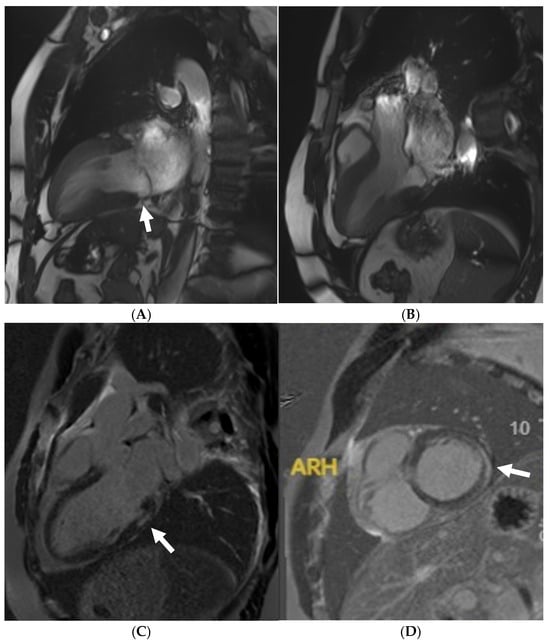

Small-vessel disease and microvascular dysfunction is a phenotypic trait in some HCM patients, often leading to a demand and supply perfusion mismatch in HCM patients (Figure 4) [58,76]. One small study also confirmed that coronary vasodilation reserve is preserved in athletes with physiological LV hypertrophy but reduced in patients with HCM [77], suggesting it may play a role when evaluating athletes in the grey zone. Data supporting routine ischaemia testing in athletes with HCM are inexistent. For HCM athletes who report chest pain without a documented LVOT obstruction (either at rest or during exercise) and epicardial coronary disease, our current practice is to perform perfusion imaging to specifically rule out microvascular dysfunction.

Figure 4. A 21 year old male that presented with chest pain during a pre-participation evaluation to join the armed forces. ECG showing biphasic ST segments in leads V1-V3, with T-wave inversion in II/III/aVF. CT coronary angiogram ruled out epicardial coronary disease. A stress echocardiogram ruled out dynamic LVOT obstruction. Echocardiogram confirmed the presence of hypertrophic cardiomyopathy, secondary to a likely pathogenic MYBPC3 variant. Cardiac MRI (3T scanner) showing septal hypertrophy (arrow) (A), extensive replacement (arrow) (B), and interstitial fibrosis in the septal segments (arrow) (C) (T1 map using a MOLLI 5b(3b)3b [3T]). Perfusion imaging (D) also identifying an extensive perfusion defect (arrow) in the hypertrophied segments, confirming microvascular dysfunction.